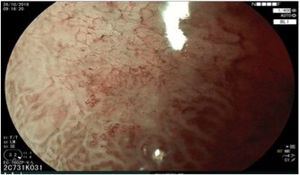

The endoscopic classification utilized to diagnose all lesions included in the present study was the Paris classification, whose validity is widely accepted by the different international consensuses and clinical guidelines. The following techniques were employed in the present study for the detection and characterization of the gastric lesions as follows: High-resolution white light endoscopy associated with a detailed and systematic review of the integrity of the gastric mucosa was initially utilized to identify lesions (Fig. 1). FICE (Flexible Spectral Imaging Colour Enhancement, Fujifilm Co., Japan) virtual chromoendoscopy or chromoendoscopy with 0.4% indigo carmine contrast staining were then employed to better characterize and delimit the lesions found (Fig. 2). In some cases, to optimize the evaluation of gastric abnormalities found (emphasizing special details, such as determining the microvascular pattern and specific alterations of the microsurface of the mucosa), minimum endoscopic image magnification, together with LCI (Linked Color Imaging, Fujifilm Co., Japan) and BLI (Blue Laser Imaging, Fujifilm Co., Japan) virtual chromoendoscopy, was utilized to show the demarcation line of the neoplastic lesion (Fig. 3), as well as microvascularization alterations (Fig. 4).